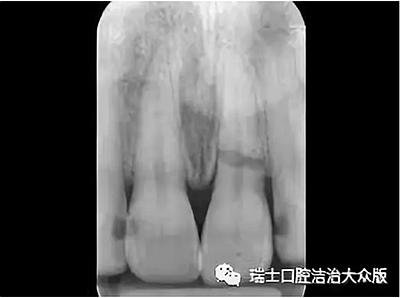

2、根折(圖5)

成人牙齒外傷了怎么應急處理?

圖5.根折

即牙根的折斷,癥狀表現(xiàn)為牙齒松動或移位,咬合不適或叩診疼痛,可伴有牙齦出血。此時應避免進食,防止牙齒的進一步移位,及時就診,醫(yī)生檢查后進行相應處理。